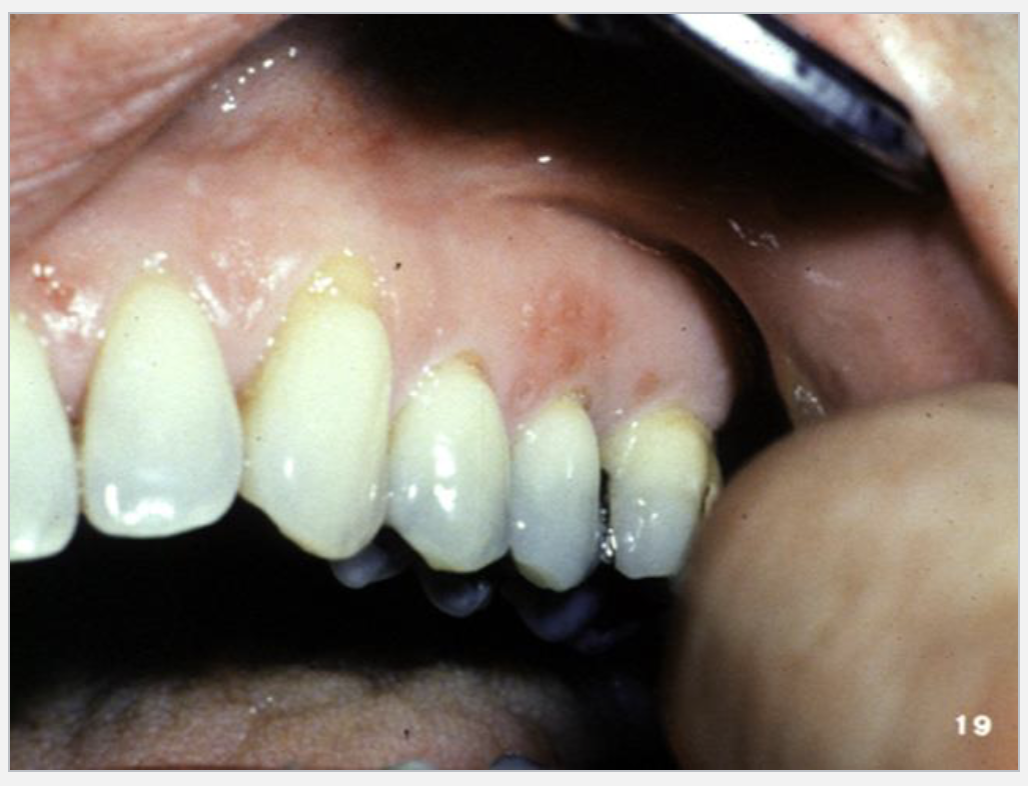

1

Q

What’s this?

A

SECONDARY HERPES SIMPLEX INFECTION